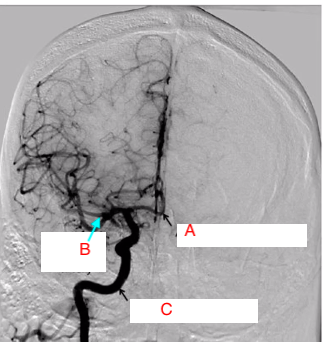

Label A-C

A: anterior cerebral artery

B: middle cererbral artery

C: internal carotid artery